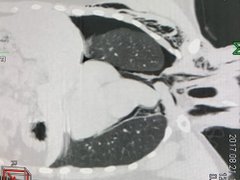

Chàng trai gãy xương sườn mà không biết

Sau va quẹt xe, chàng trai chỉ đau phần mềm sơ nên không đi khám. Sau nhiều ngày, thấy khó thở, anh đến bệnh viện mới biết gãy xương sườn.